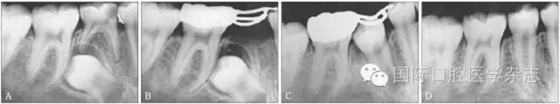

圖3為一因“乳磨牙爛牙”前來(lái)就診兒童的X線片檢查。影像學(xué)檢查顯示:第二乳磨牙近中深齲,近遠(yuǎn)中牙根吸收均不明顯,但遠(yuǎn)中根尖病變引起了第二前磨牙萌出方向的改變。臨床處置:及時(shí)拔除了齲壞的第二乳磨牙,制作第一恒磨牙帶環(huán)絲圈間隙維持器,3個(gè)月后復(fù)診,X線片顯示第二前磨牙萌出方向逐漸正向調(diào)整;6個(gè)月后復(fù)診,第二前磨牙基本正位萌出;1年后復(fù)診,第二前磨牙調(diào)整到位。從圖3的病例可以看出:乳磨牙根尖周病變會(huì)引起恒牙萌出方向的改變,出現(xiàn)咬合紊亂的潛在性表現(xiàn),但臨床上通過(guò)去除病灶牙與簡(jiǎn)單的間隙維持、未實(shí)施牽引助萌即糾正了該病例潛在性的咬合紊亂發(fā)生。

A:下頜第二乳磨牙近中齲,X線片顯示遠(yuǎn)中根尖周病變引起繼承恒牙萌出方向改變;B:擬及時(shí)拔除病變的下頜第二乳磨牙,行間隙維持;C:拔除病變的下頜第二乳磨牙間隙維持后一段時(shí)間,繼承恒牙萌出方向發(fā)生正向改變;D:繼承恒牙正位萌出。

圖3 乳牙根尖炎癥引起繼承恒牙萌出方向改變的典型病例

Fig 3 Typical case oferuptive direction change caused by periapical infection of primary tooth